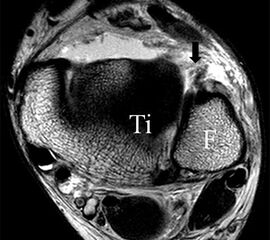

Die Kombination aus 3 Tesla Hochfeldtechnik und/oder Verwendung hochauflösender Spulen (Empfangseinheiten des Signals) erhöht die Signalausbeute. Dies erlaubt mit akzeptablen Messzeiten (3-4 Minuten pro Sequenz) im Routinebetrieb eine Darstellung mit einer Schichtdicke von 1-2 mm und einer Ortsauflösung von 0,2 x 0,2 mm in der Schichtebene in den anatomisch am besten zeichnenden 2D Turbospinechosequenzen. Der Unterschied der diagnostischen Wertigkeit zwischen einer kernspintomographischen „Standarduntersuchung“ und einer HR-MRT wird besonders in der chondralen Diagnostik sichtbar (Abb. 1 a-c). Unter Verwendung von 3D Sequenzen, die jedoch entscheidende Schwächen bei der Darstellung der Ligamente aufweisen, werden sogar Schichtdicken weit im Submillimeterbreich erreicht. Eine weitere Erörterung der Sequenz spezifischen Eigenheiten soll jedoch an dieser Stelle unterbleiben.

Jedoch findet man sich auch hier mit dem Problem der in den Standard-Projektionen schräg verlaufenden Syndesmose konfrontiert. Der oligofaszikuläre Aspekt der vorderen Syndesmose kann in der axialen Schnittebene eine zum Verwechseln ähnliche Morphologie wie eine Ruptur aufweisen (Abb. 15 b und c). Doppelangulierte Schnitte entlang der Achse (schräg koronar/schräg sagittal) lassen hingegen eine eindeutige Beurteilung der Bandstrukturen zu (Abb. 16) und verbessern die Syndesmosendiagnostik.

Bezogen auf die Transversalebene verläuft die Syndesmose ca. 30° schräg cranio-caudal anguliert (Abb. 15 a). Häufig lassen sich drei Hauptfaszikel differenzieren: das kürzeste superiore, das stärkste mittlere und das längste kaudale Faserbündel. Ein akzessorisches Bündel, das anteriore-inferiore, tibiofibulare Ligament (AITFL) oder auch Bassett-Ligament wird in 80-94% der Patienten nachgewiesen 8. Dies weist einen unmittelbaren Bezug zur anterolateralen Talusschulter auf (Abb. 17). In Kombination mit einer Außenbandinstabilität und konsekutivem, talarem Vorschub kann dieses zu einem Impingement an der anterolateralen Taluskante führen mit nachfolgender chondraler oder osteochondraler Läsion.